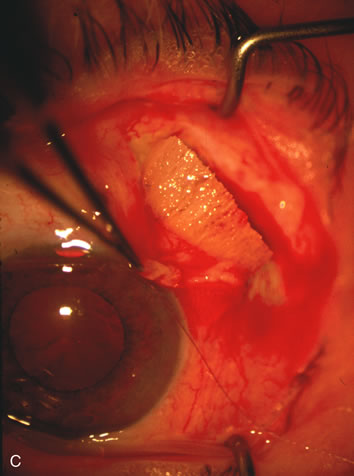

Fig. 1. The anatomic advantage of small incision cataract surgery for the glaucoma patient. A. Long-term bleb function with a large cataract incision is difficult to achieve with either ECCE-trabeculectomy or trabeculectomy followed later by ECCE. This bleb failed to form sufficiently when combined with large incision ECCE. The inflammation, bleeding, and long-term wound healing with stimulation of fibroblasts associated with this technique are more likely to cause bleb failure. In addition, the increased iris manipulation necessary to deliver the nucleus and subsequent iris repair adds to the long-term breakdown of the blood aqueous barrier. B and C. Two-site phacotrabeculectomy has the advantage of small incision cataract surgery combined with separate site trabeculectomy. The incision size is one third the size of the standard ECCE. The inflammation is less severe, and cataract wound healing is confined to the temporal area. Visual rehabilitation with phacoemulsification and foldable IOL is much faster. Phacoemulsification allows successful lens extraction even in the unfriendly environment of a smaller pupil compared with ECCE. The trabeculectomy is performed in an entirely different site, well away from the wound healing associated with temporal phacoemulsification. The likelihood of this filter functioning long-term is greater than with ECCE-trabeculectomy. D. The surgeon also has the option of single-site phacotrabeculectomy with foldable IOL. Both the lens extraction and trabeculectomy are performed through one small 3.5-mm limbal incision.

Fig. 3. Partial bleb failure following clear corneal phacoemulsification with foldable IOL. A. Preoperative bleb appearance prior to temporal lens extraction. Preoperative IOP was 12 mm Hg on no antiglaucoma medications. Time from 5-FU trabeculectomy surgery to lens extraction was one year. B. Bleb appearance 2 months after clear corneal cataract surgery with topical anesthesia. Following lens extraction, increased vascularity was noted along with decreased size of the filtering bleb. IOP increased to 20 mm Hg as early as 2 weeks after surgery, necessitating topical antiglaucoma therapy. C. High magnification view of bleb before lens extraction demonstrates diffuse pale bleb. D. High magnification view of bleb 2 months after surgery. There are vessels surrounding the nasal side of the bleb and the overall bleb size is smaller.